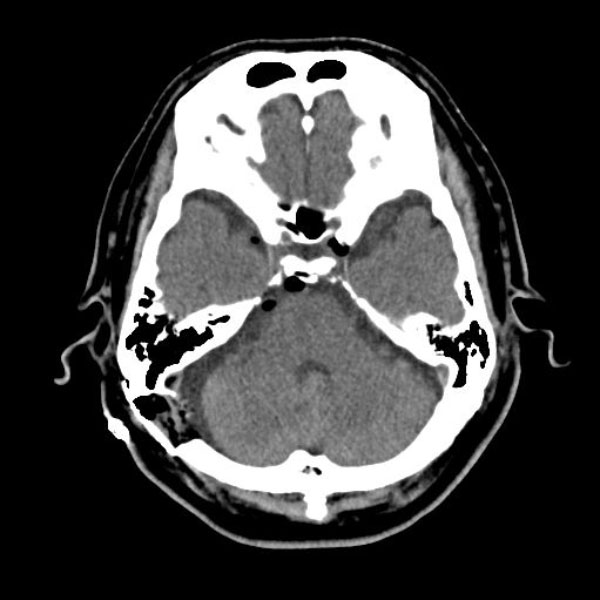

580

兵庫県の病院

'26年2月

70代

右三叉神経痛

手術前